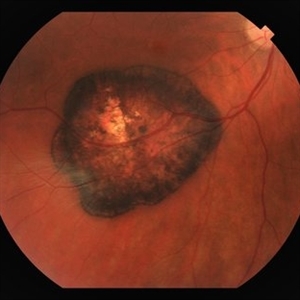

Choroidal Metastasis from Breast Cancer

Oct 1 2019 by John S. King, MD

60-year-old white female with four year history of breast cancer associated with metastasis to many organs including the CNS, was sent her to r/o melanoma, found on routine exam. Visual acuity was HM; there was NSC/PSC; there was a unilateral, large choroidal lesion in the posterior pole that was yellow, well circumscribed, with plateau configuration associated with SRF adn heme.

Photographer: Kay Dalby

Imaging device: Optos CA

Condition/keywords: breast cancer, choroidal lesions, choroidal metastasis